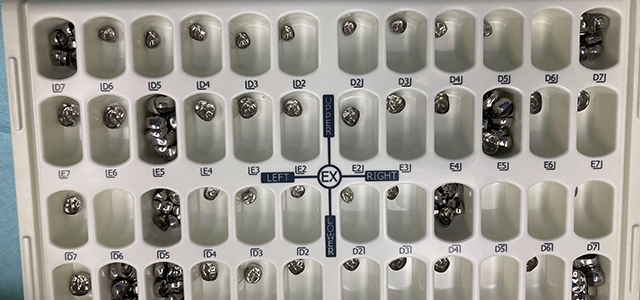

3岁小女孩当天完成6颗龋齿修复

小朋友乳磨牙通常六岁左右开始替换,常规的补牙很难持久。针对3岁女孩牙齿缺损较大和涉及牙齿相邻龋洞,为了缓解疼痛,康贝佳口腔医院进行了全麻下预成冠修复,让孩子可以正常咀嚼食物,促进恒牙正常替换以及颌骨发育。

全麻下修复后,小女孩牙齿焕然一新,全程无疼痛,舒适睡眠状态下一次性完成6颗牙齿的治疗,减少了多次诊疗时间,预成冠保护乳牙健康恒牙才会更健康,小朋友有了美观健康的牙齿,开心不得了,牙齿再也不疼了,家长也放心下来。